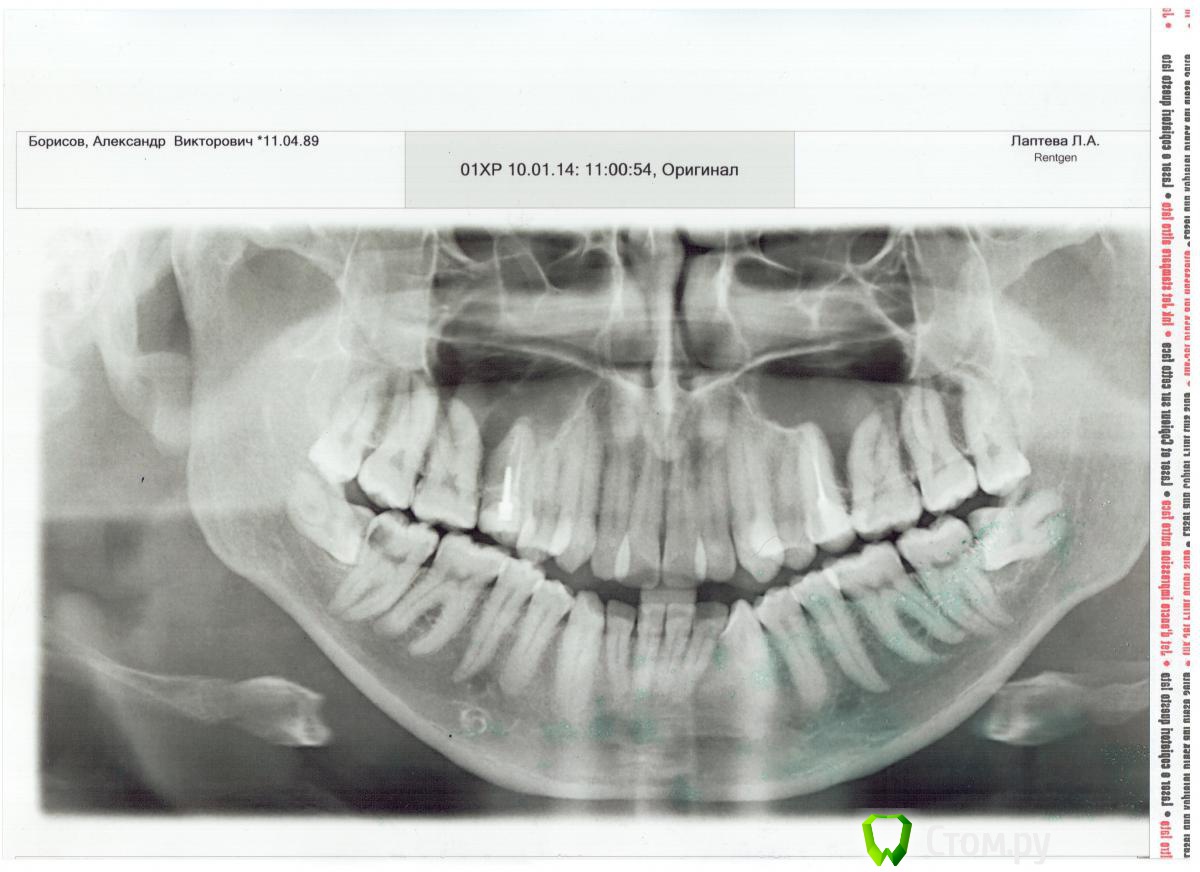

lordofhell Опубликовано 26 февраля, 2014 Автор Поделиться Опубликовано 26 февраля, 2014 (изменено) Можно оставить в большинстве случаев. Ну вот это уже обнадёживает хоть немного. Сейчас боли уже нет. Она была где-то неделю и носила спонтанный характер. То есть пью горячий чай, резко появляется боль, держится секунд 20 и пропадает, пью этот же чай дальше, боли нет. Или вышел на улицу на мороз, вдохнул морозный воздух ртом и опять резка боль на несколько десятков секунд и также резко проходит, дальше дышу ртом уже безболезненно. Или просто спонтанно проявлялась без видимых раздражителей. Снимок прикладываю. К сожалению, ему уже месяц и пару дней он у меня ездил на заднем сидении машины и попадал под прямые солнечные лучи, появились синие разводы. С левой стороны зуб тоже вырос вбок, но до соседнего не достал. Там была другая проблема- еда попадала "под десну", не знаю как это правильно обозвать, зуб тоже едва выступал из десны и пища попала между ним и десной и благополучно там загноилась. Тоже все убеждали, что зуб надо удалять, что это будут одни мучения и т.д. и т.п. В результате один хирург посмотрел на это, вырезал кусочек десны над этим зубом и отпустил с богом. Десна заросла и ещё немного растянулась, обнажив зуб. Прошло больше года уже, пища туда больше не попадает. Изменено 26 февраля, 2014 пользователем lordofhell Ссылка на комментарий

igorstom Опубликовано 27 февраля, 2014 Поделиться Опубликовано 27 февраля, 2014 Удалять. С такими лежащими горизонтально "восьмерками" недолго и "семёрки" потерять. Найдите опытного хирурга, и всё будет ништяк. Ссылка на комментарий